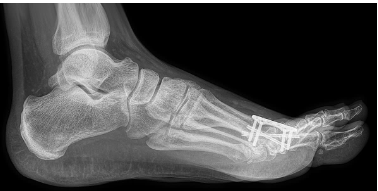

Great toe fusion (From the surgeon's web site): Not day procedure; plates and screws inserted to hold bones in place; can walk afterwards, but lying down with foot elevated recommended for 2 weeks. Dressings off in 2 weeks, but wearing overshoe recommended for another 4-5 weeks. Xray after 6 weeks to see that bones have knitted. "3 months until full recovery".